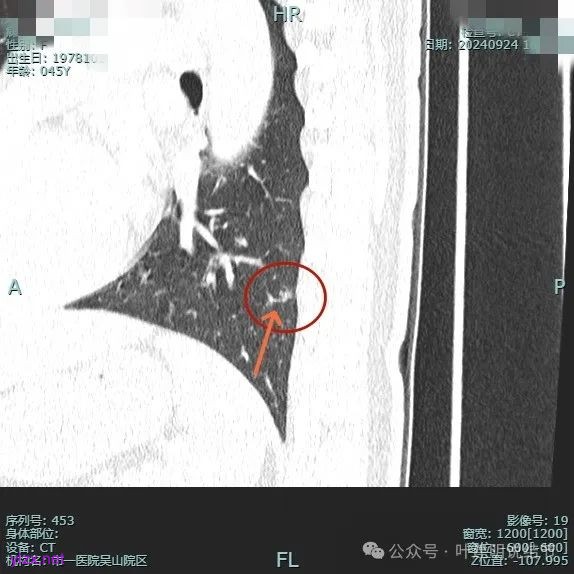

时间很快到了2025年3月,结友又来我门诊复查,我还以为她在别处开了刀了呢,结果并没有,说是与家人商量后决定吃中药三个月看看能不能好。我们来看看再复查的情况,中药有没有起作用:

总体感觉三处病灶边缘的淡磨玻璃成分好转不太明显了,实性成分较前略显致密点,大小与形态是说不上显著变化的。所以有几点可以肯定:1、消炎没有效;2、中药没有用;3、考虑多原发肺癌,且为浸润性腺癌可能性大些,得手术!